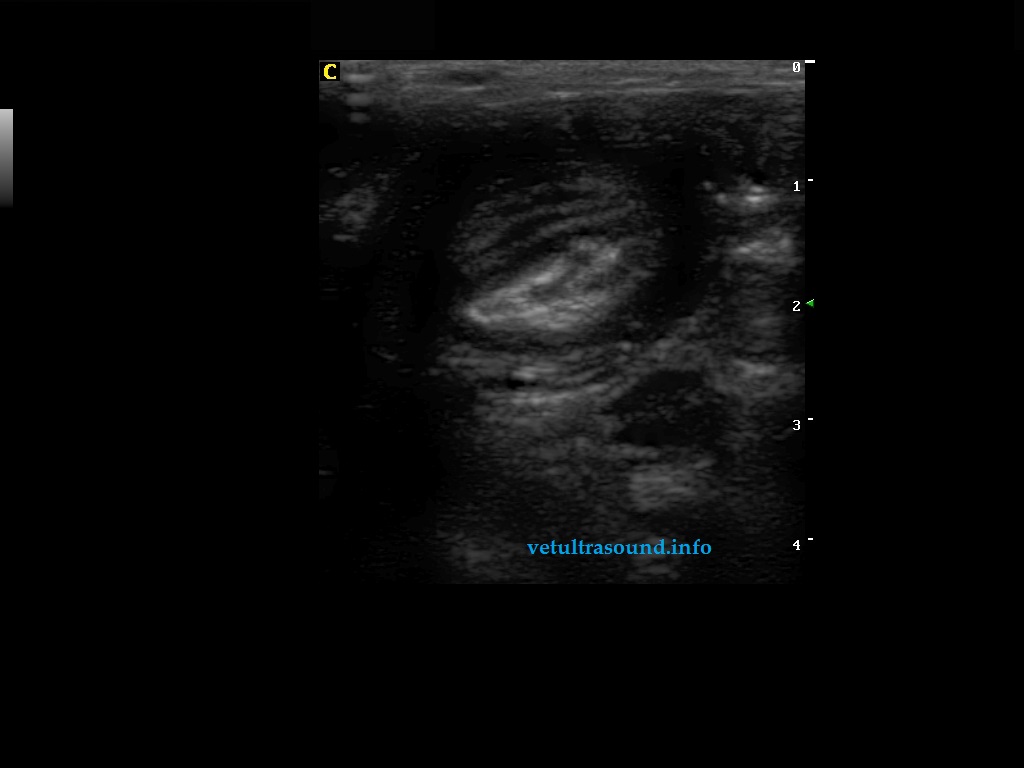

Findings: Distention of large part of the small intestine, caused by intussusception. The blood flow in the mesenteric arteries which supplied the intussusception was normal. The mesenteric lymphnodes were enlarged. A small amount of ascistic fluid was noted.

Ευρήματα: Στον υπερηχοτομογραφικό έλεγχο της κοιλίας βρέθηκε παρουσία εγκολεασμού σε τμήμα του λεπτού εντέρου. Η αιμάτωση των μεσεντέριων αγγείων του εγκολεσθέντος τμήματος εκτιμήθηκε φυσιολογική. Οι μεσεντέριοι λεμφαδένες βρέθηκαν διογκωμένοι με αντιδραστική ηχομορφολογία. Υπήρχε μικρή ποσότητα ασκιτικού υγρού. Οι υπόλοιπες εντερικές έλικες που αφορούσαν το τμήμα του λεπτού εντέρου πριν τον εγκολεασμό βρέθηκαν διατεταμένες .